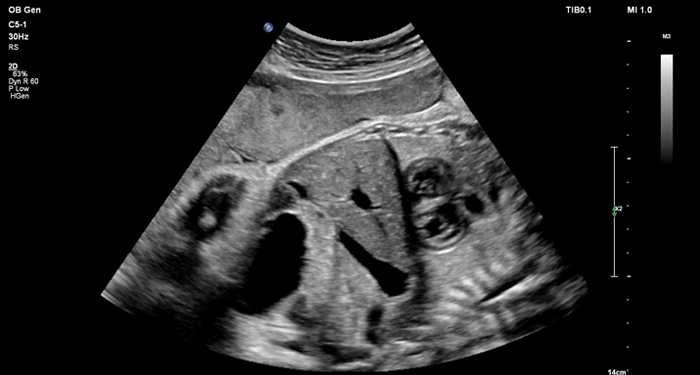

At the touch of a button, the new MaxVue high-definition display brings extraordinary visualisation of anatomy with 1,179,648 additional image pixels compared to a standard 4:3 display format mode. MaxVue enhances ultrasound viewing during interventional procedures and provides 38% more viewing area to optimise the display of dual, side/side, biplane, and scrolling imaging modes.

MaxVue offers a 38% greater viewing area.